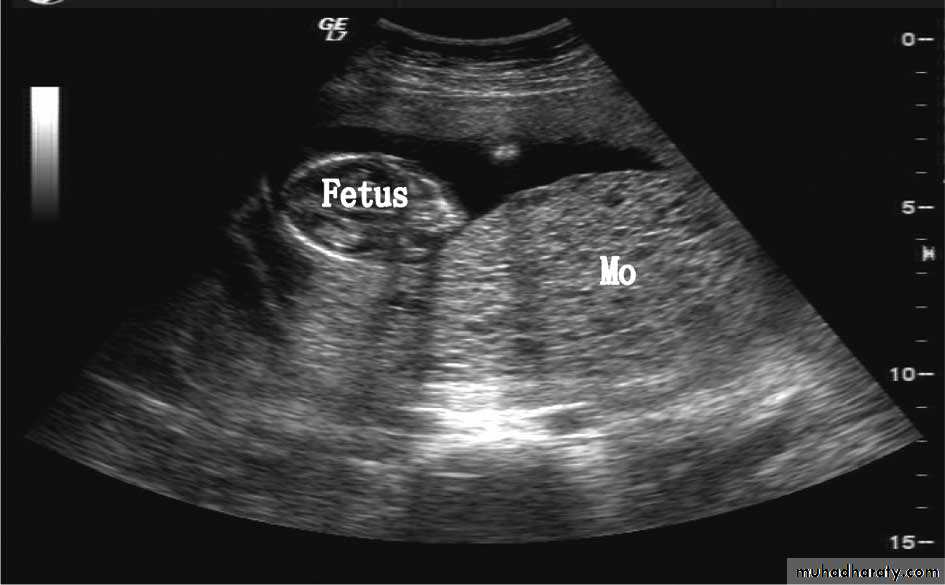

US of partial H.mole

This slide show patial H.mole + vesicles + fetal tissue